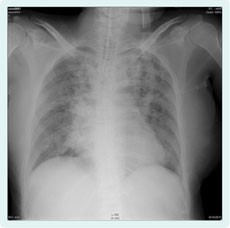

In spite of administration of antibiotics, her respiratory state and oxygenation worsened. The chest X-ray showed alveolar infiltrates in the left upper lobe; it also showed multifocal, bilateral nodular opacities (Figure 1).

Figure 1. 33-year-old woman’s chest X-ray showed alveolar infiltrate with air bronchogram in left upper lobe, and showed multifocal, bilateral nodular opacities